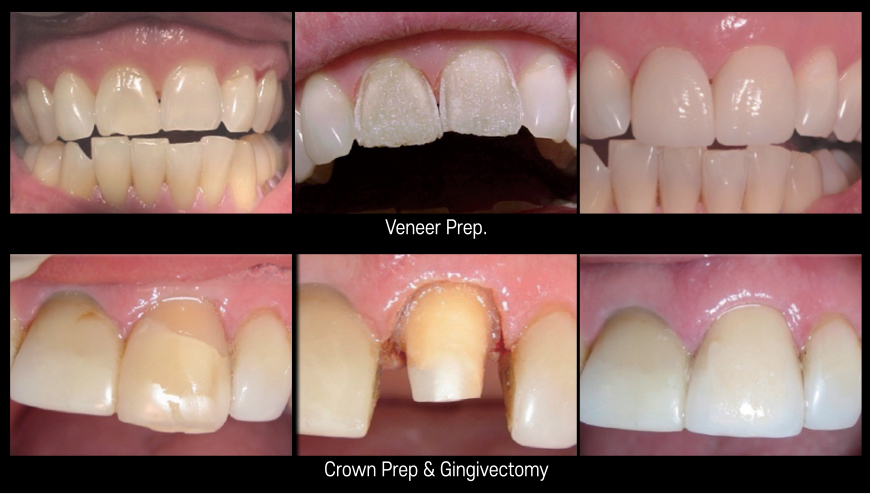

Cavity Prep., Veneer Prep., Crown Removal, Resin Filling

Surface Preparation Comparison

Gingivectomy, Gum Bleaching, Frenectomy, Crown Lengthening, Fibroma Removal

- Allows precise and customized design to match the natural gingival contour

Crown Lengthening – Functional

Contour osseous tissues1 to achieve necessary biologic width

Gingivectomy